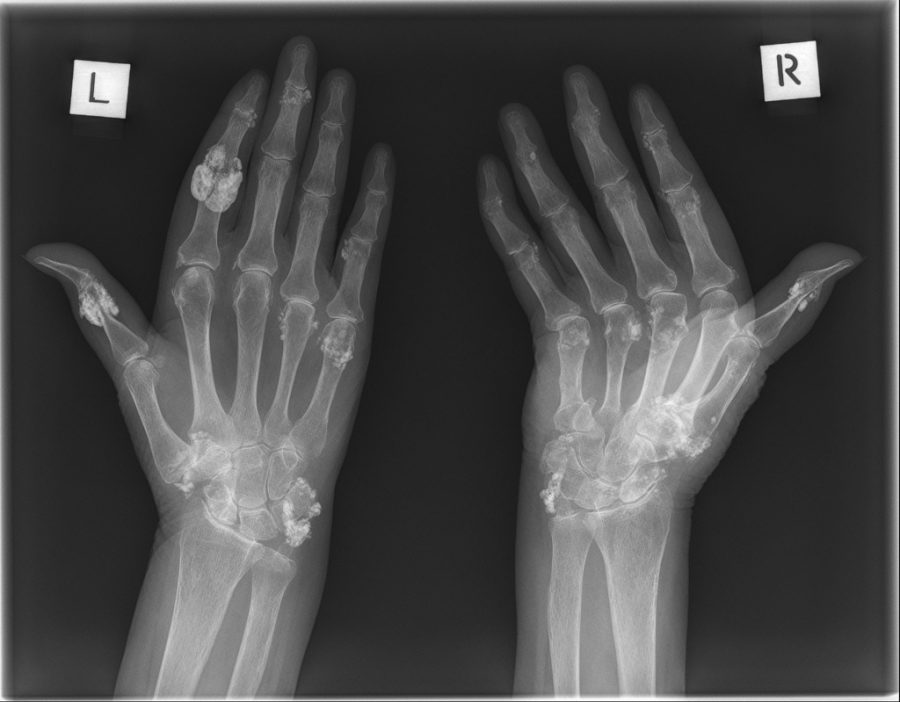

Scleroderma Hands Xray Ild Scleroderma Radiology It is a leading cause of mortality and at autopsy the lung is reportedly involved in. Right ventricular (rv) dysfunction can be primary (direct myocardial involvement) or secondary (due to pah, lv dysfunction, or ild). Interstitial lung disease (ild) is a frequent complication of systemic sclerosis (ssc) that is often progressive and has a poor prognosis. 23 in a retrospective. Ild Scleroderma Radiology.

Scleroderma hand manifestations Image Ild Scleroderma Radiology Right ventricular (rv) dysfunction can be primary (direct myocardial involvement) or secondary (due to pah, lv dysfunction, or ild). Interstitial lung disease (ild) is a frequent complication of systemic sclerosis (ssc) that is often progressive and has a poor prognosis. 23 in a retrospective study of hrcts from patients in the australian scleroderma cohort study, extensive disease involving more than. Ild Scleroderma Radiology.